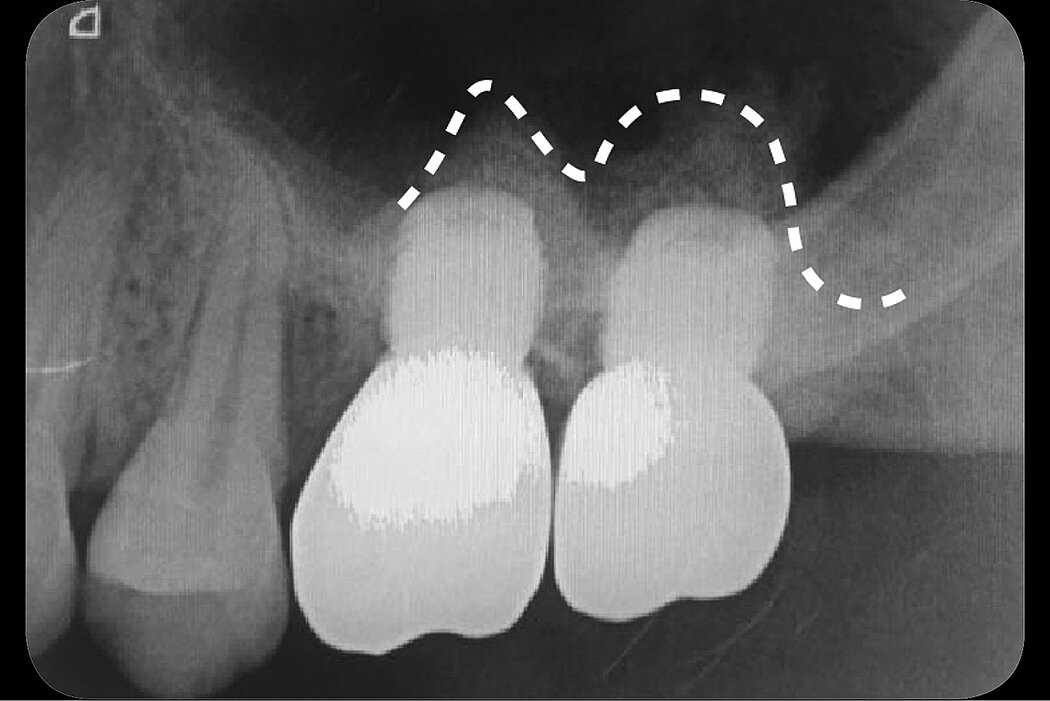

Double crestal sinus floor elevation

Alveolar bone resorption in posteriormaxilla and maxillary sinus pneumatization always challenges the implant placement. Maxillary sinus floor elevation and onlay bone grafting are the regular methods for solving these problems. Two main approaches for the maxillary sinus floor elevation procedure are now widely used in dental clinics. Lateral antrostomy is mostly used in severe alveolar bone resorption but one of the drawbacks of the lateral antrostomy is that it requires the raising of a large flap for surgical access. The crestal approach is considered to be a more conservative method. This case report demonstrates a minimally invasive technique for the management of vertical ridge defects (less than 1mm) in the posterior maxilla. The double-crestal-approach provides clinicians a simple, convenient and minimally invasive approach compared to the regular lateral antrostomy.

Treatment was carried out under local anaesthesia with local buccal and palatal infiltrations. The proposed implant site was marked with a trephine drill. The depth was controlled within the alveolar bone to protect the sinus membrane from perforation. Then the round bone block was gently tapped and pushed into the maxillary sinus using the sinus lift osteotome. By using the trephine drill, the cut bone block can be used. While the bone block was gently pushed into sinus, the sinus membrane was elevated at the same time. The boneblock provides the osteoblast while the connected sinus membrane provides the blood supply. The osteoblast and blood supply are the key factors forbone ossification. The Schneiderian membrane near to the bone block was slightly dissected using an antralcurette. Then the bone block was elevated again for about 4mm. A spaceis created by the intruded bone block. This space is then grafted with Geistlich Bio-Oss®. Geistlich Bio-Gide® was adapted too verlay the osteotomy site. The second sinus floor elevation was performed six months later with the same procedure.